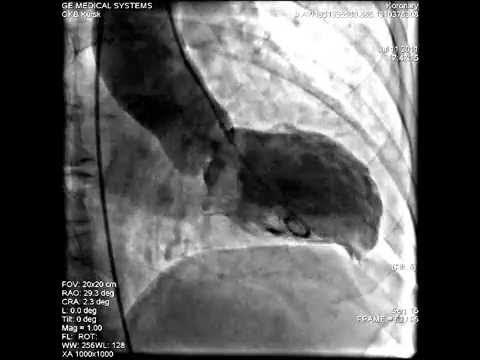

Пластическая операция при аневризме левого желудочка